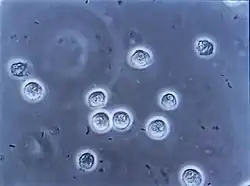

Uropathogenic E. coli from the gut is the cause of 80–85% of community-acquired urinary tract infections,[31] with Staphylococcus saprophyticus being the cause in 5–10%.[4] Rarely they may be due to viral or fungal infections.[32] Healthcare-associated urinary tract infections (mostly related to urinary catheterization) involve a much broader range of pathogens including: E. coli (27%), Klebsiella (11%), Pseudomonas (11%), the fungal pathogen Candida albicans (9%), and Enterococcus (7%) among others.[7][33][34] During recent years of intensive care, Enterococcus spp. have several times been found as the primary cause of urinary tract infection, suggested related to broad treatment with cephalosporin antibiotics against which they are tolerant.[35][36][37] Urinary tract infections due to Staphylococcus aureus typically occur secondary to blood-borne infections.[10] Chlamydia trachomatis and Mycoplasma genitalium can infect the urethra but not the bladder.[38] These infections are usually classified as a urethritis rather than urinary tract infection.[39]